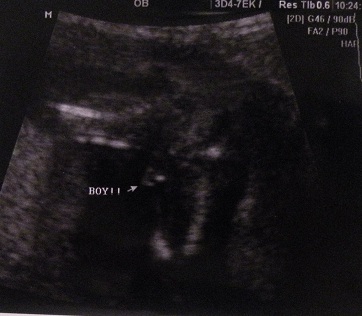

I just had an u/s done when I was 15w2d, where the tech told us we were having a boy. I was truly shocked bc according to Ramzi method baby came up girl (implanted on left side), the HB has always been high (at 8 wks was 150something, 12 wks it was 171, & is now 158-160), other OWT's/tests came out girl, plus my gut feeling said girl & I've not been wrong in all my pregnancies. Here are the potty shot pics, ANY possible way this could end up a girl?

Attachment 5962